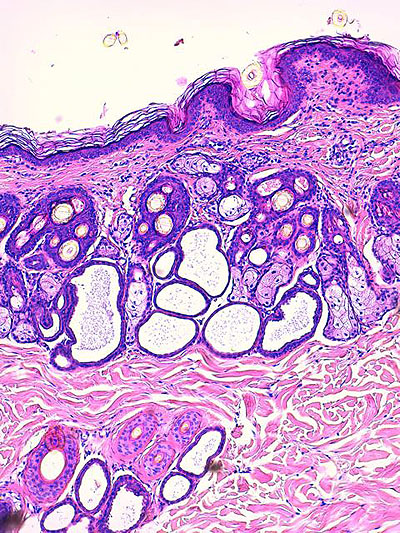

Photo 4 : (Hémalun Eosine X 200) : Hyperplasie des infundibula et isthmes folliculaires,

des canaux et des glandes sébacés; inflammation mononucléée du pourtour isthmique

des follicules pileux et des glandes sébacées; le cycle folliculaire est normal.

Légendes de la Photo 4 :

- Pointe de flèche rouge = tige pilaire dans isthme folliculaire

- Étoile rouge = fundus de glande sudorale épitrichiale

- Étoile turquoise = lobules de glande sébacée hyperplasique

- Flèche double noire = canal sébacé hyperplasique et hyperkératosique (orthokératose)

- Carré rouge = follicule pileux en phase anagène

- Étoile rouge = infiltrat inflammatoire lympho-plasmocytaire péri-isthmique